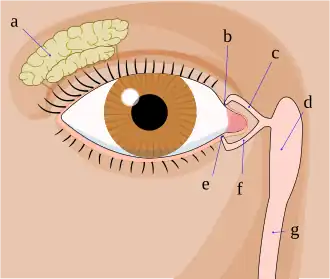

a. tear gland / lacrimal gland,

b. superior lacrimal punctum,

c. superior lacrimal canal,

d. tear sac / lacrimal sac,

e. inferior lacrimal punctum,

f. inferior lacrimal canal,

g. nasolacrimal canal

Enlargement of the lacrimal gland, located superotemporally within the orbit, produces protrusion of the eye inferiorly and medially (away from the location of the lacrimal gland). Lacrimal gland may be enlarged from inflammation (e.g. sarcoid) or neoplasm (e.g. lymphoma or adenoid cystic carcinoma).[11]